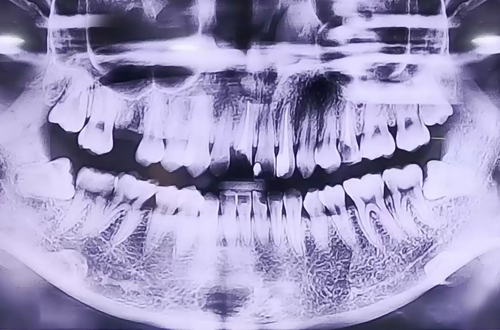

부러진 앞니 임플란트

BEFORE

야간진료 시간에 앞니가 부러져 급하게 내원해 주셨던 환자분이십니다.

처음엔 자연 치아를 최대한 살리는 방향의 치료를 고려했지만 치아 상태가 그러기 어려워 부러진 앞니를 발치하고 임플란트를 통해 복원하는 방향으로 치료를 진행중이십니다.

현재 식립한 임플란트가 제대로 자리 잡을때까지 임시 치아를 제작해 씌워드린 상태이며, 추후 임플란트가 단단히 자리 잡고 보철이 완성되면 다음 진료일지로 찾아뵙도록 하겠습니다. ^^